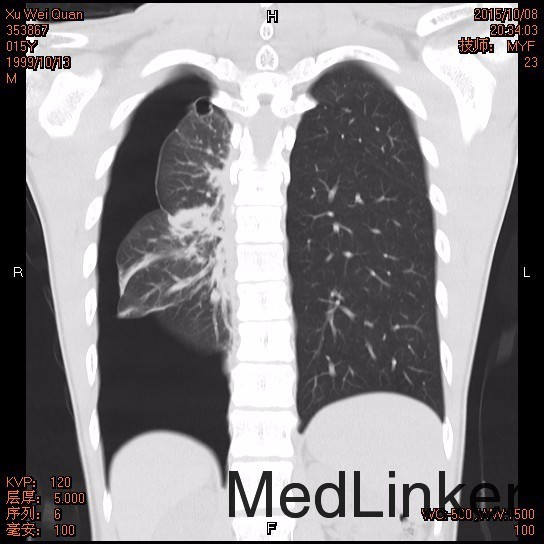

查体:患者呈瘦高类型,胸廓无畸形,肋间隙变窄,左肺叩诊呈清音,呼吸音清,右肺叩诊过清音,呼吸音弱,双肺未闻及异常呼吸音及干、湿罗音。辅查: 胸部CT1.右侧气胸,右肺组织受压缩约80-90%;右侧胸腔内见一引流管留置; 2.双上肺肺大疱; 3.右侧腋下、胸壁皮下气肿。

诊断:右侧肺大疱并自发性气胸 治疗:完善相关术前检查,行“胸腔镜右上肺楔形切除术+胸腔粘连松解术”,术程顺利,术后恢复可,现患者一般情况可,正常进食,无胸闷气促等不适。查体生命体征平稳,切口II/甲愈合,予出院。